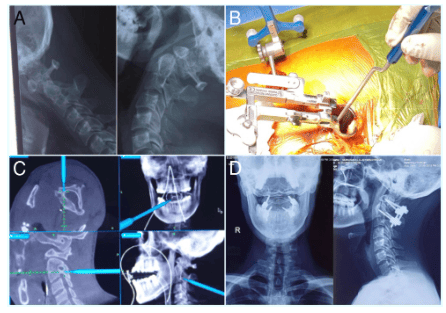

Minimally invasive C1-lateral mass- C2 pedicle screw fixation (B) for a case of Reducible atlantoaxial subluxation (A) with C2-3 klippel-feil and narrow C2 pedicles. O-arm helps in accurate placement of a C2 screw through the narrow pedicle minimizing the risk of vertebral artery injury (C). D – post-operative X-ray